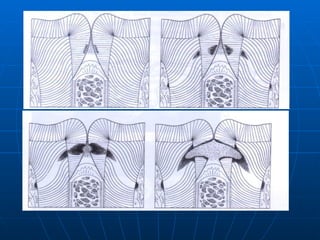

“ Forward-backward” classification is considered as  graphical representation of the pathway of dental caries.   ENAMEL First component of enamel to be involved in carious process is the  interprismatic substance . The disintegrating chemicals will proceed via the substance, causing the enamel prism to be undermined. The resultant caries involvement in enamel will have cone shape. In concave surface (pit and fissures) base towards DEJ. In convex surfaces (smooth surface) base away from DEJ.

DENTIN First component to be involved in dentin is  protoplasmic extension  within the dentinal tubules. These protoplasmic extension have their maximum space at the DEJ, but as they approach the pulp chamber and root canal walls, the  tubules become more densely arrange with fewer interconnections . So caries cone in dentin will have their base towards DEJ.

Decay starts in enamel then it involves the dentin. Wherever the caries cone in enamel is larger or at least the size as that of dentin, it is called forward decay (pit decay) However the carious process in dentin progresses much faster than in enamel, so the cone in dentin tends to spread laterally creating undermined enamel. In addition decay can attack enamel from its dentinal side. At this stage it becomes backward decay.

“ Forward-backward” classificationis considered as graphical representation of the pathway of dental caries. ENAMEL First component of enamel to be involved in carious process is the interprismatic substance . The disintegrating chemicals will proceed via the substance, causing the enamel prism to be undermined. The resultant caries involvement in enamel will have cone shape. In concave surface (pit and fissures) base towards DEJ. In convex surfaces (smooth surface) base away from DEJ.

DENTIN First componentto be involved in dentin is protoplasmic extension within the dentinal tubules. These protoplasmic extension have their maximum space at the DEJ, but as they approach the pulp chamber and root canal walls, the tubules become more densely arrange with fewer interconnections . So caries cone in dentin will have their base towards DEJ.

Decay starts inenamel then it involves the dentin. Wherever the caries cone in enamel is larger or at least the size as that of dentin, it is called forward decay (pit decay) However the carious process in dentin progresses much faster than in enamel, so the cone in dentin tends to spread laterally creating undermined enamel. In addition decay can attack enamel from its dentinal side. At this stage it becomes backward decay.